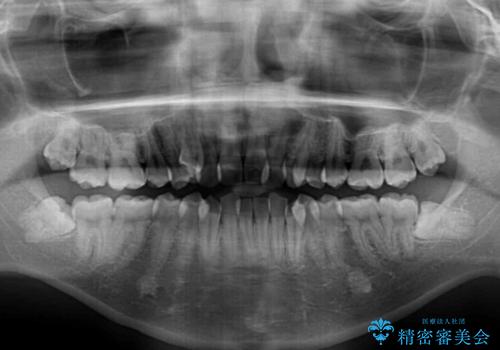

上下ともに八重歯が顕著であり、前歯のクロスバイトがあったため、上下左右の第一小臼歯4本を抜歯し、ワイヤー装置での抜歯矯正を行うこととしました。